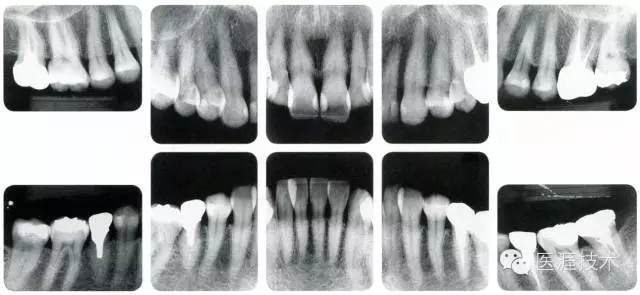

56歲牙周炎男性的臨床照片

640.webp (15).jpg

正在服用高血壓藥中的56歲男性。菌斑控制得不好。通過牙周探診,全頜有4~6mm的牙周袋,在X光片中可以看到全頜中度牙槽骨吸收,磨牙處一個(gè)地方是重度牙槽骨吸收。通過比較牙周病進(jìn)展?fàn)顟B(tài),邊緣部有大范圍浮腫(發(fā)紅、腫脹),和纖維性肥厚。這也可能是服用中的降壓藥的副作用導(dǎo)致的。因?yàn)檠例l、牙槽骨比較厚,牙齦呈架子狀。